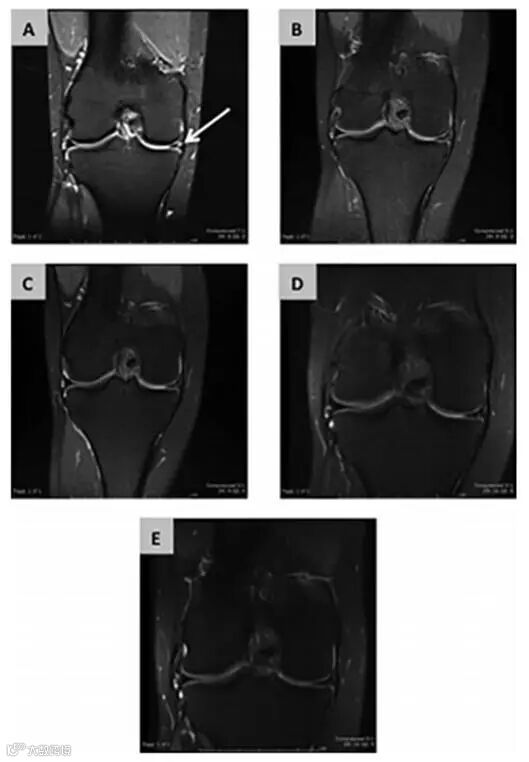

(图b术后3个月;图c术后6个月;图d术后12个月;图e术后24个月)